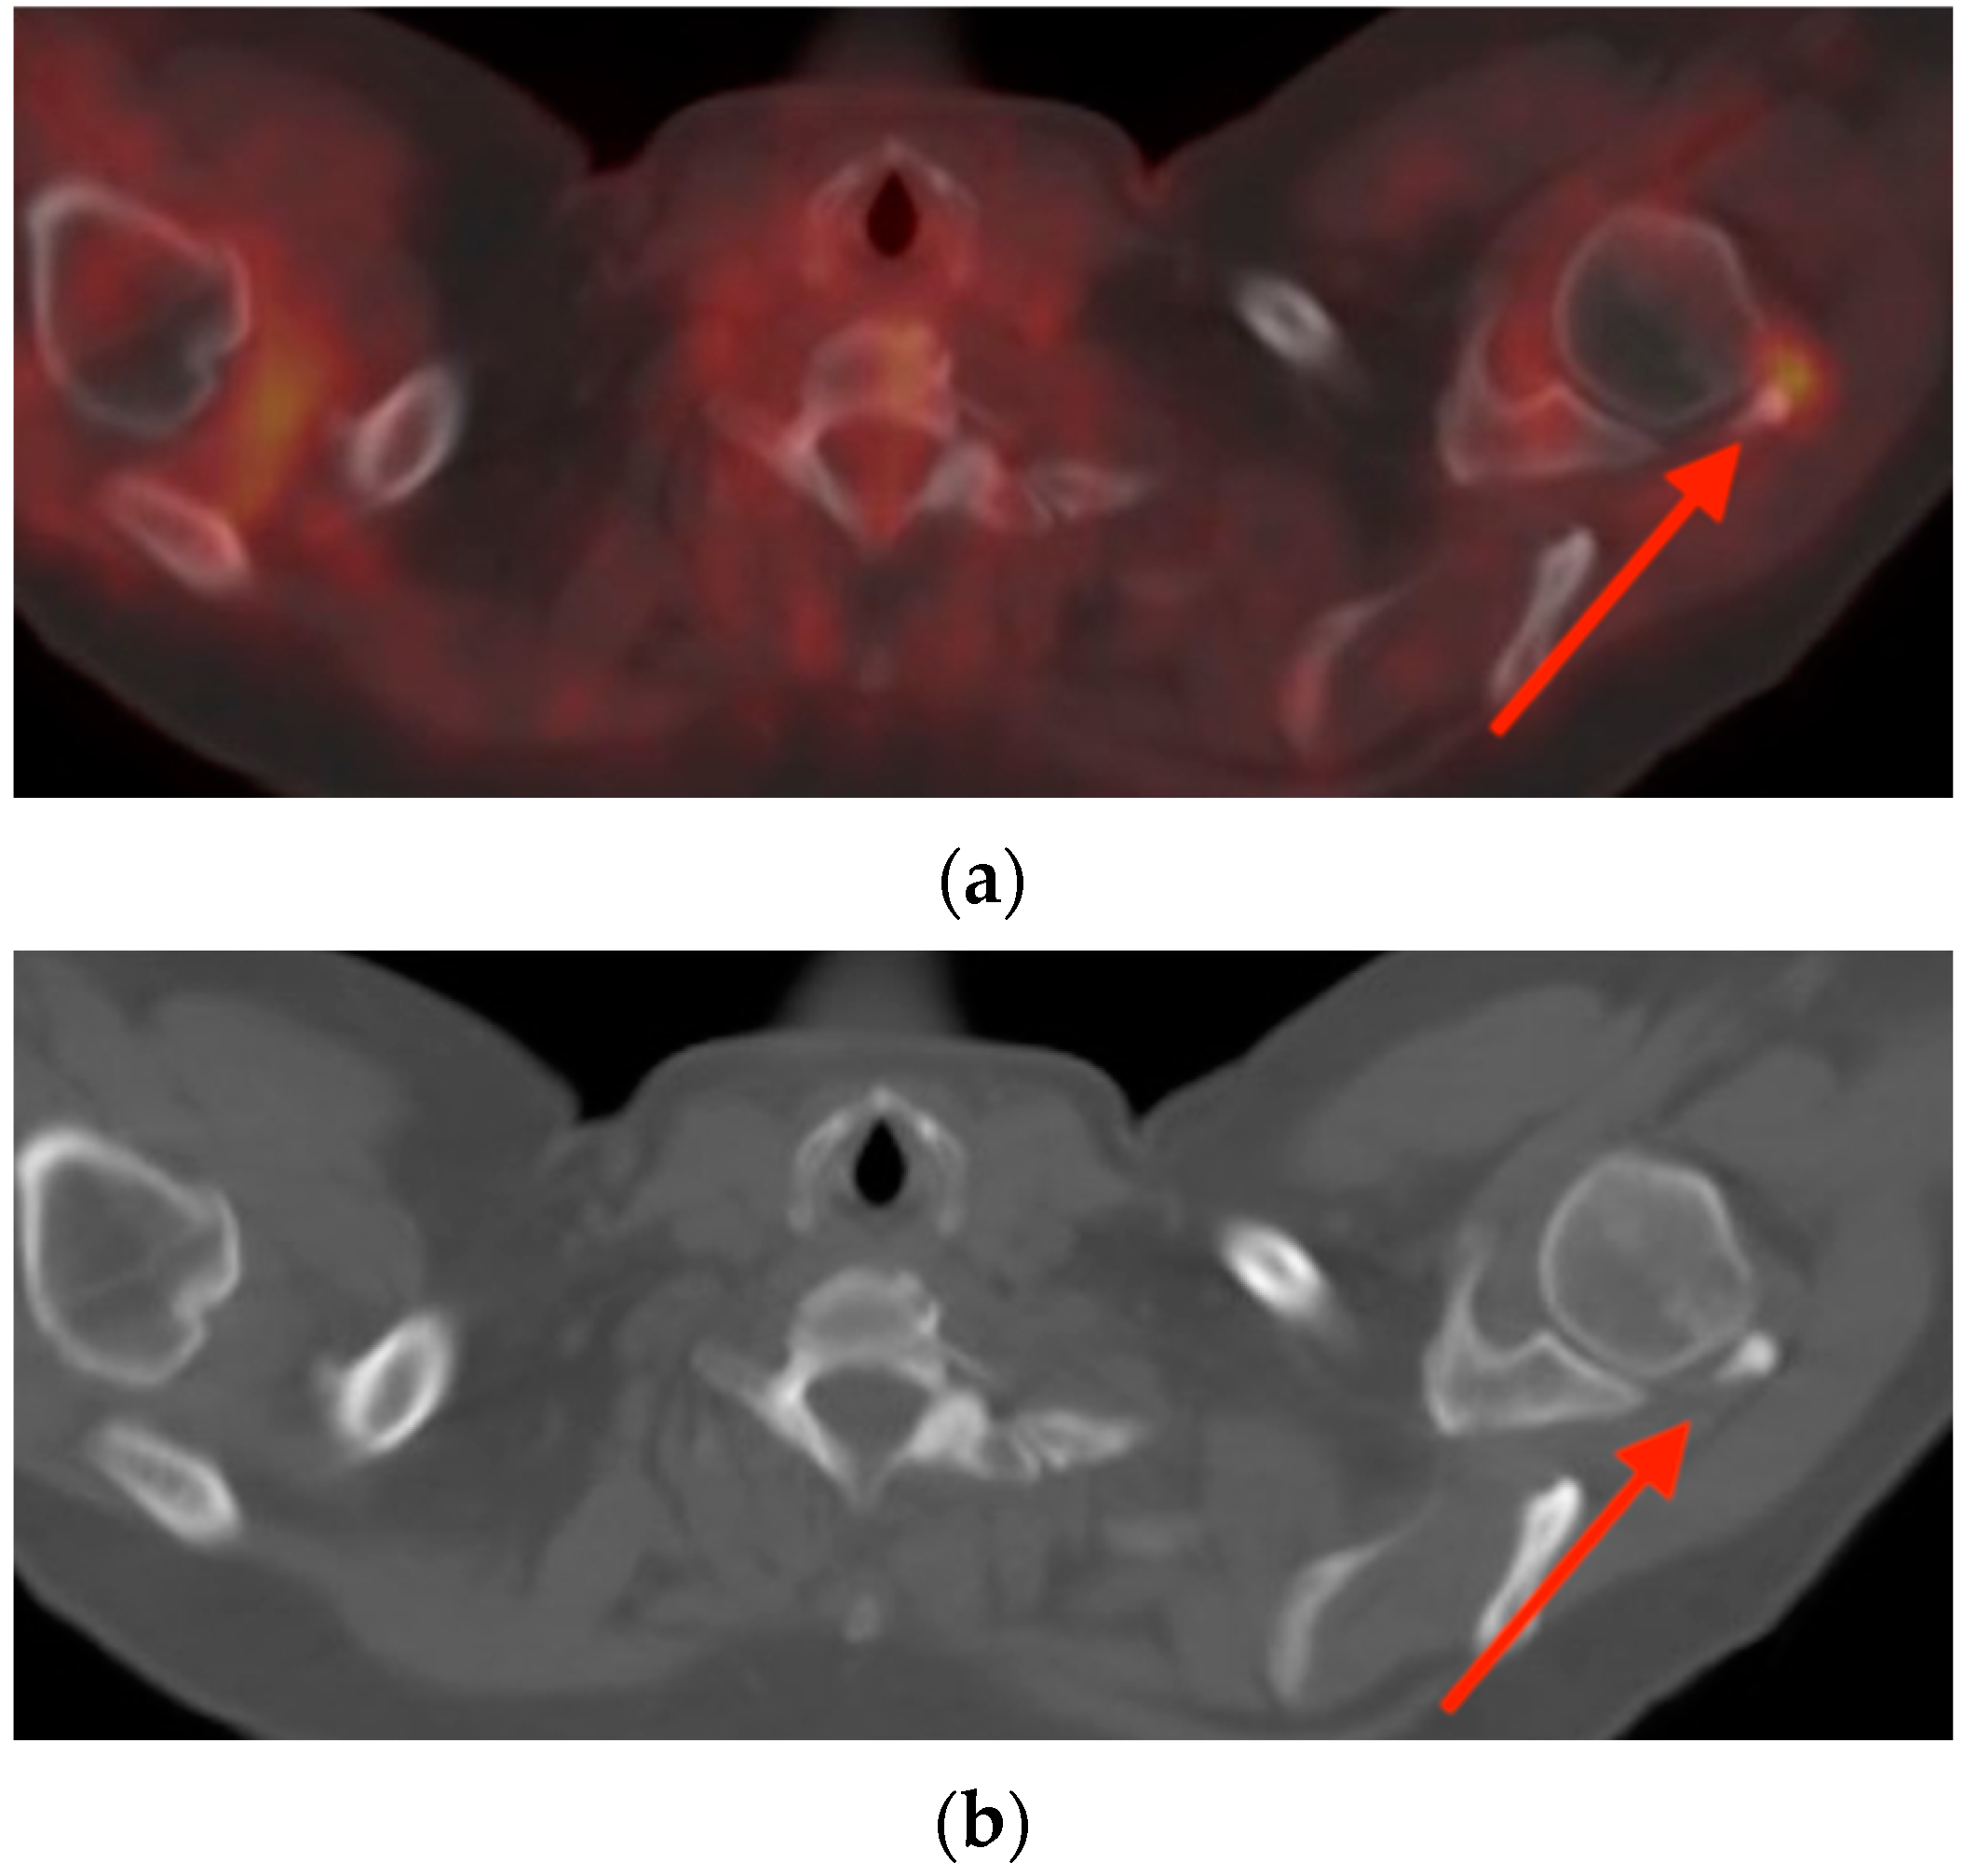

2.3. Enchondroma

- Mulligan, M.E. How to Diagnose Enchondroma, Bone Infarct, and Chondrosarcoma. Curr. Probl. Diagn. Radiol. 2019, 48, 262–273. [Google Scholar] [CrossRef] [PubMed]

- Cheung, H.; Yechoor, A.; Behnia, F.; Abadi, A.B.; Khodarahmi, I.; Soltanolkotabi, M.; Shafiei, M.; Chalian, M. Common Skeletal Neoplasms and Nonneoplastic Lesions at 18F-FDG PET/CT. Radiographics 2022, 42, 250–267. [Google Scholar] [CrossRef]

- Subhawong, T.K.; Winn, A.; Shemesh, S.S.; Pretell-Mazzini, J. F-18 FDG PET differentiation of benign from malignant chondroid neoplasms: A systematic review of the literature. Skelet. Radiol. 2017, 46, 1233–1239. [Google Scholar] [CrossRef]